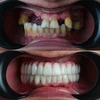

%100 hasta memnuniyeti odaklı çalışan ve her bir hasta için özel tedavi planlaması prensibi ile hastalarının yaşamına dokunan Dt. Bende Doğan, bu zamana kadar binlerce smile design, implant, restorasyon ve kanal tedavisi uygulamasına imza atarken, hasta referansıyla çalışma disiplini ile faaliyet göstermektedir.

Zirkonyum uygulamalar

Porselen uygulamaları

Laminate veneer